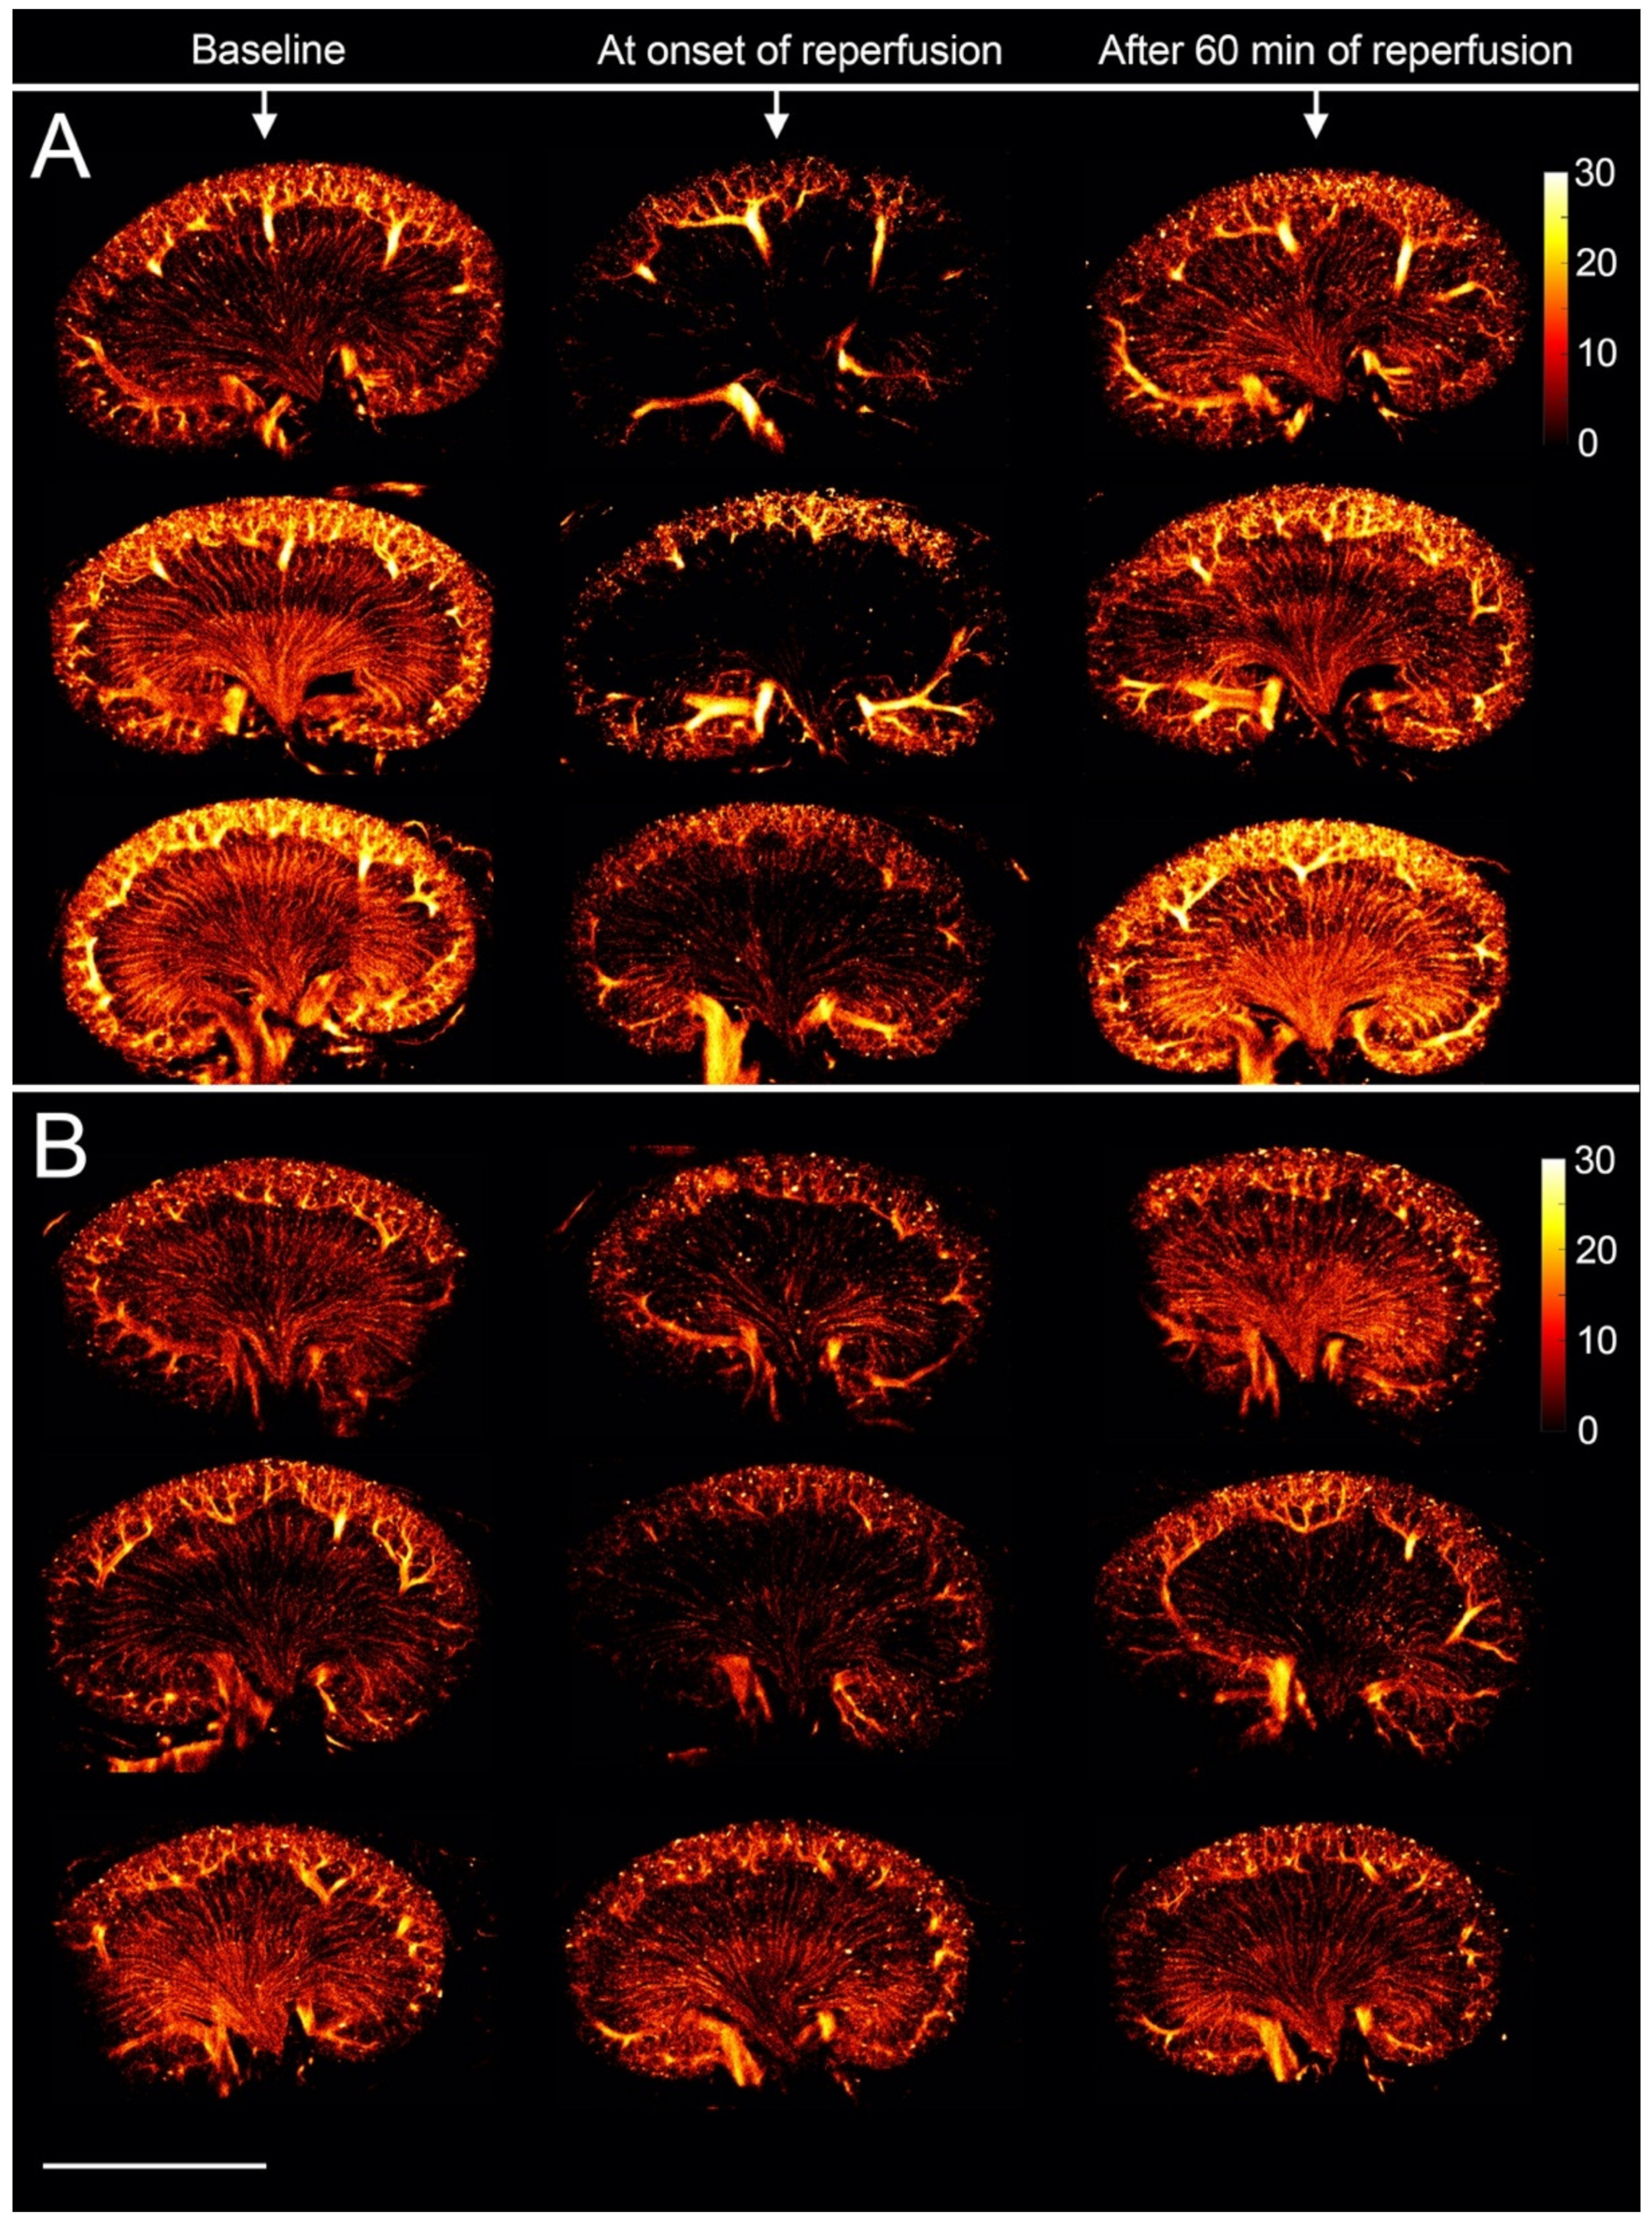

3.2. The Renal Microvasculature after Ischemia with Reperfusion